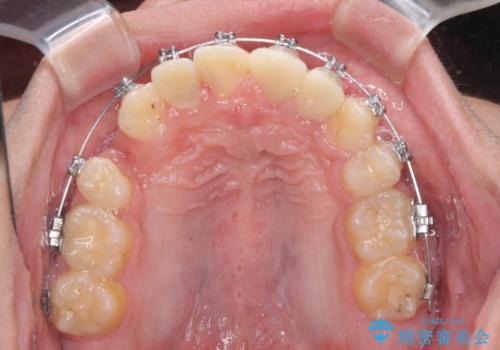

- 矯正装置

- メタルブラケット

矯正治療は、むし歯が酷く抜歯が望ましい歯を1本抜歯して、ワイヤー装置にて整えることとしました。

矯正治療後は上顎前歯4本をオールセラミッククラウンにて補綴治療を行うこととしました。